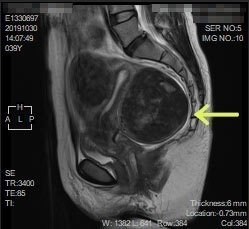

子宮筋腫と卵巣腫瘍 その6 Mri 日々 楽天ブログ

Mri画像と病院探し 彡 子宮筋腫 激痛とのタタカイ 楽天ブログ